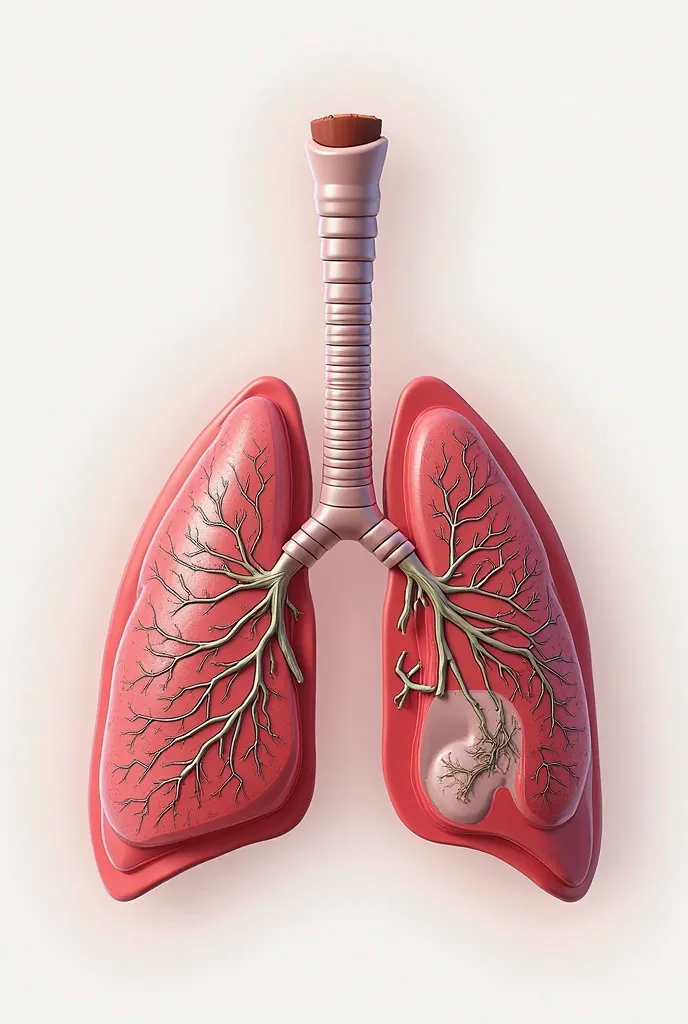

Generate a lungs, the right side lungs is healthy vibrant color surrounded with

Generate a lungs, the right side lungs is healthy vibrant color surrounded with fresh air. On the left side make the lungs damage or pollution of elements in smoking. Add some symbols of no smoking in the pulution part, and add some clean air in the right side lungs

On the left side make the lungs damage or pollution of elements in smoking

Add some symbols of no smoking in the pulution part

and add some clean air in the right side lungs